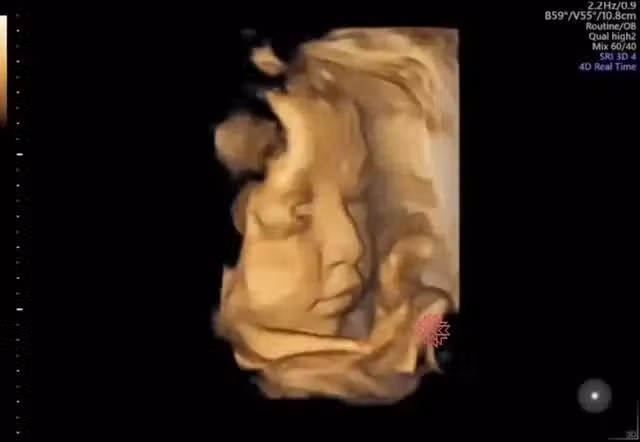

寶寶在肚子裡「會睜開眼嗎」?超音波影片曝光「神奇瞬間」融化媽咪心:還露微笑太可愛~

話是這麼說沒錯,但能夠看到寶寶在子宮內的任何舉動,都足以讓當媽的當爹的感到興奮了~而蘇醫師分享的這段影片中,不但寶寶有短暫睜眼一下下(如上圖),還可以看到寶寶嘟嘴、微笑等表情呢!